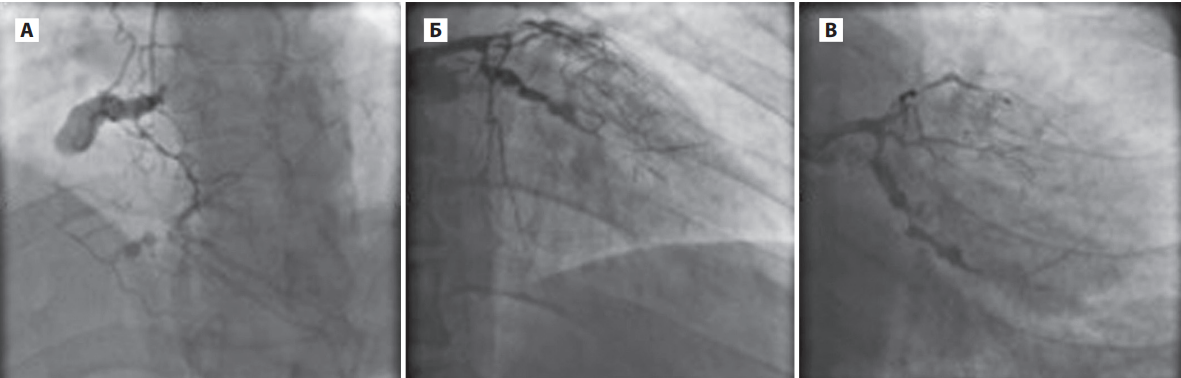

Там всё же смогли выполнить коронарографию, и что же? Все артерии сердца в стенозах от 50 до 100% (т.е. есть и окклюзии - полное перекрытие просвета). Ствол левой коронарной артерии сужен на 55%.

Сосуды, кровоснабжающие мозг - все в стенозах от 45 до 95%, не уцелел ни один.

Ангиография артерий нижних конечностей: везде стенозы от 55 до 80%.

Ангиография почечных артерий: в проксимальной трети стеноз 75%, в левой - ранее был установлен стент, т.е. там тоже был стеноз .

В подключичных артериях тоже стенозы от 50 до 90%.

В общем, нет практически ни одного сосудистого бассейна, который бы не пострадал.